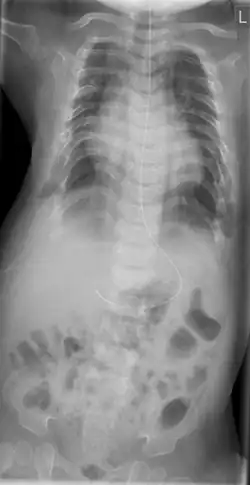

Röntgenbild Thorax-Abdomen eines elf Monate alten Neugeborenen mit Asphyxierender Thoraxdysplasie Jeune

Die klinische Verdachtsdiagnose wird im Röntgenbild gesichert. Diagnostische Kriterien sind:[1][2][14]

• Kurze, horizontal verlaufende Rippen

• Schmale Beckenschaufeln mit dreizackartiger Begrenzung des Unterrandes, Pfannendach horizontal verlaufend und spornartig nach kaudal weisend

• Vorzeitige Verknöcherung der Femurepiphyse

• Distal betont verkürzte Röhrenknochen

• Zapfenepiphysen der Mittelphalangen